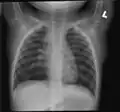

Obliterative bronchiolitis involving the terminal airways.

Obliterative bronchiolitis involving the terminal airways

Obliterative bronchiolitis is often diagnosed based on the symptoms of obstructive lung disease following lung injury. The definitive diagnosis is through biopsy, but due to the variable distribution of lesions, leading to falsely negative tests, and invasive nature of this procedure it is often not performed.[6][11] Several tests are often needed to diagnose obliterative bronchiolitis, including spirometry, diffusing capacity of the lung tests (DLCO), lung volume tests, chest X-rays, high-resolution CT (HRCT), and lung biopsy.[11][4]